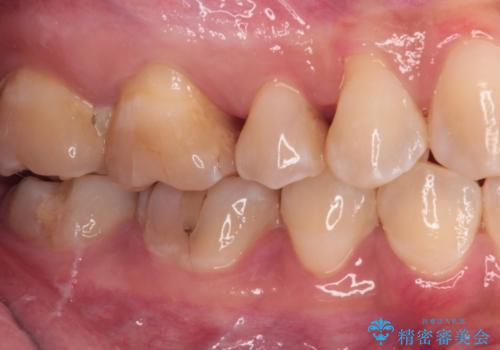

治療後は物が挟まることもなく、フロスが引っかかったり出血したりすることが減りました。